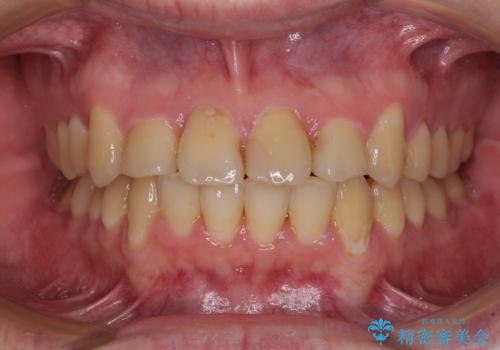

- 上下のデコボコと前歯のクロスバイトを改善したいとのことで来院された患者様です。

マウスピース矯正での自己管理には自信がないとのことで、ワイヤー装置による矯正治療を行うこととしました。

デコボコの程度は強かったのですが、口元の突出感はなかったため、非抜歯矯正としました。